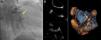

A 72-year old woman with a history of mechanical aortic prosthesis since 2010 and early infective prosthetic endocarditis (medical treatment) was hospitalized for acute heart failure in February 2015. Transesophageal echocardiography showed a severe paravalvular leak in the posterior portion of the aortic prosthesis (Figure 1A, arrow) and a pseudoaneurysm with fistulization to the left ventricle (LV) and aorta (Figure 1B, arrow), moderate mitral regurgitation and mild LV systolic dysfunction. Surgery was considered high risk and percutaneous closure of the paravalvular leak was attempted. The procedure was guided by fluoroscopy and transesophageal echocardiography. After confirming the stability of the device (Amplatzer® Vascular Plug II 12 mm/9 mm) and reduction of the paravalvular leak without functional compromise of the mechanical prosthesis (Figures 2A and 2B, arrow), the device was released. Minutes after deployment, the device migrated into the LV (Figure 3A, arrow and Supplementary data online, Movie S1). The device could not be retrieved (Figure 3B, arrow). Echocardiography images showed the device lodged beneath the posterior mitral leaflet, entrapped in the subvalvular mitral apparatus, with no significant compromise of mitral valve function (Figures 4A, arrow and 4B, arrow and Supplementary data online, Movie S2). Follow-up echocardiographies showed the device still in the same position. The patient died of sepsis due to a Clostridium difficile infection 58 days after admission (one month after the procedure). This case illustrates a rare and dramatic complication of percutaneous leak closure, but without significant hemodynamic impact on mitral valve and LV function.